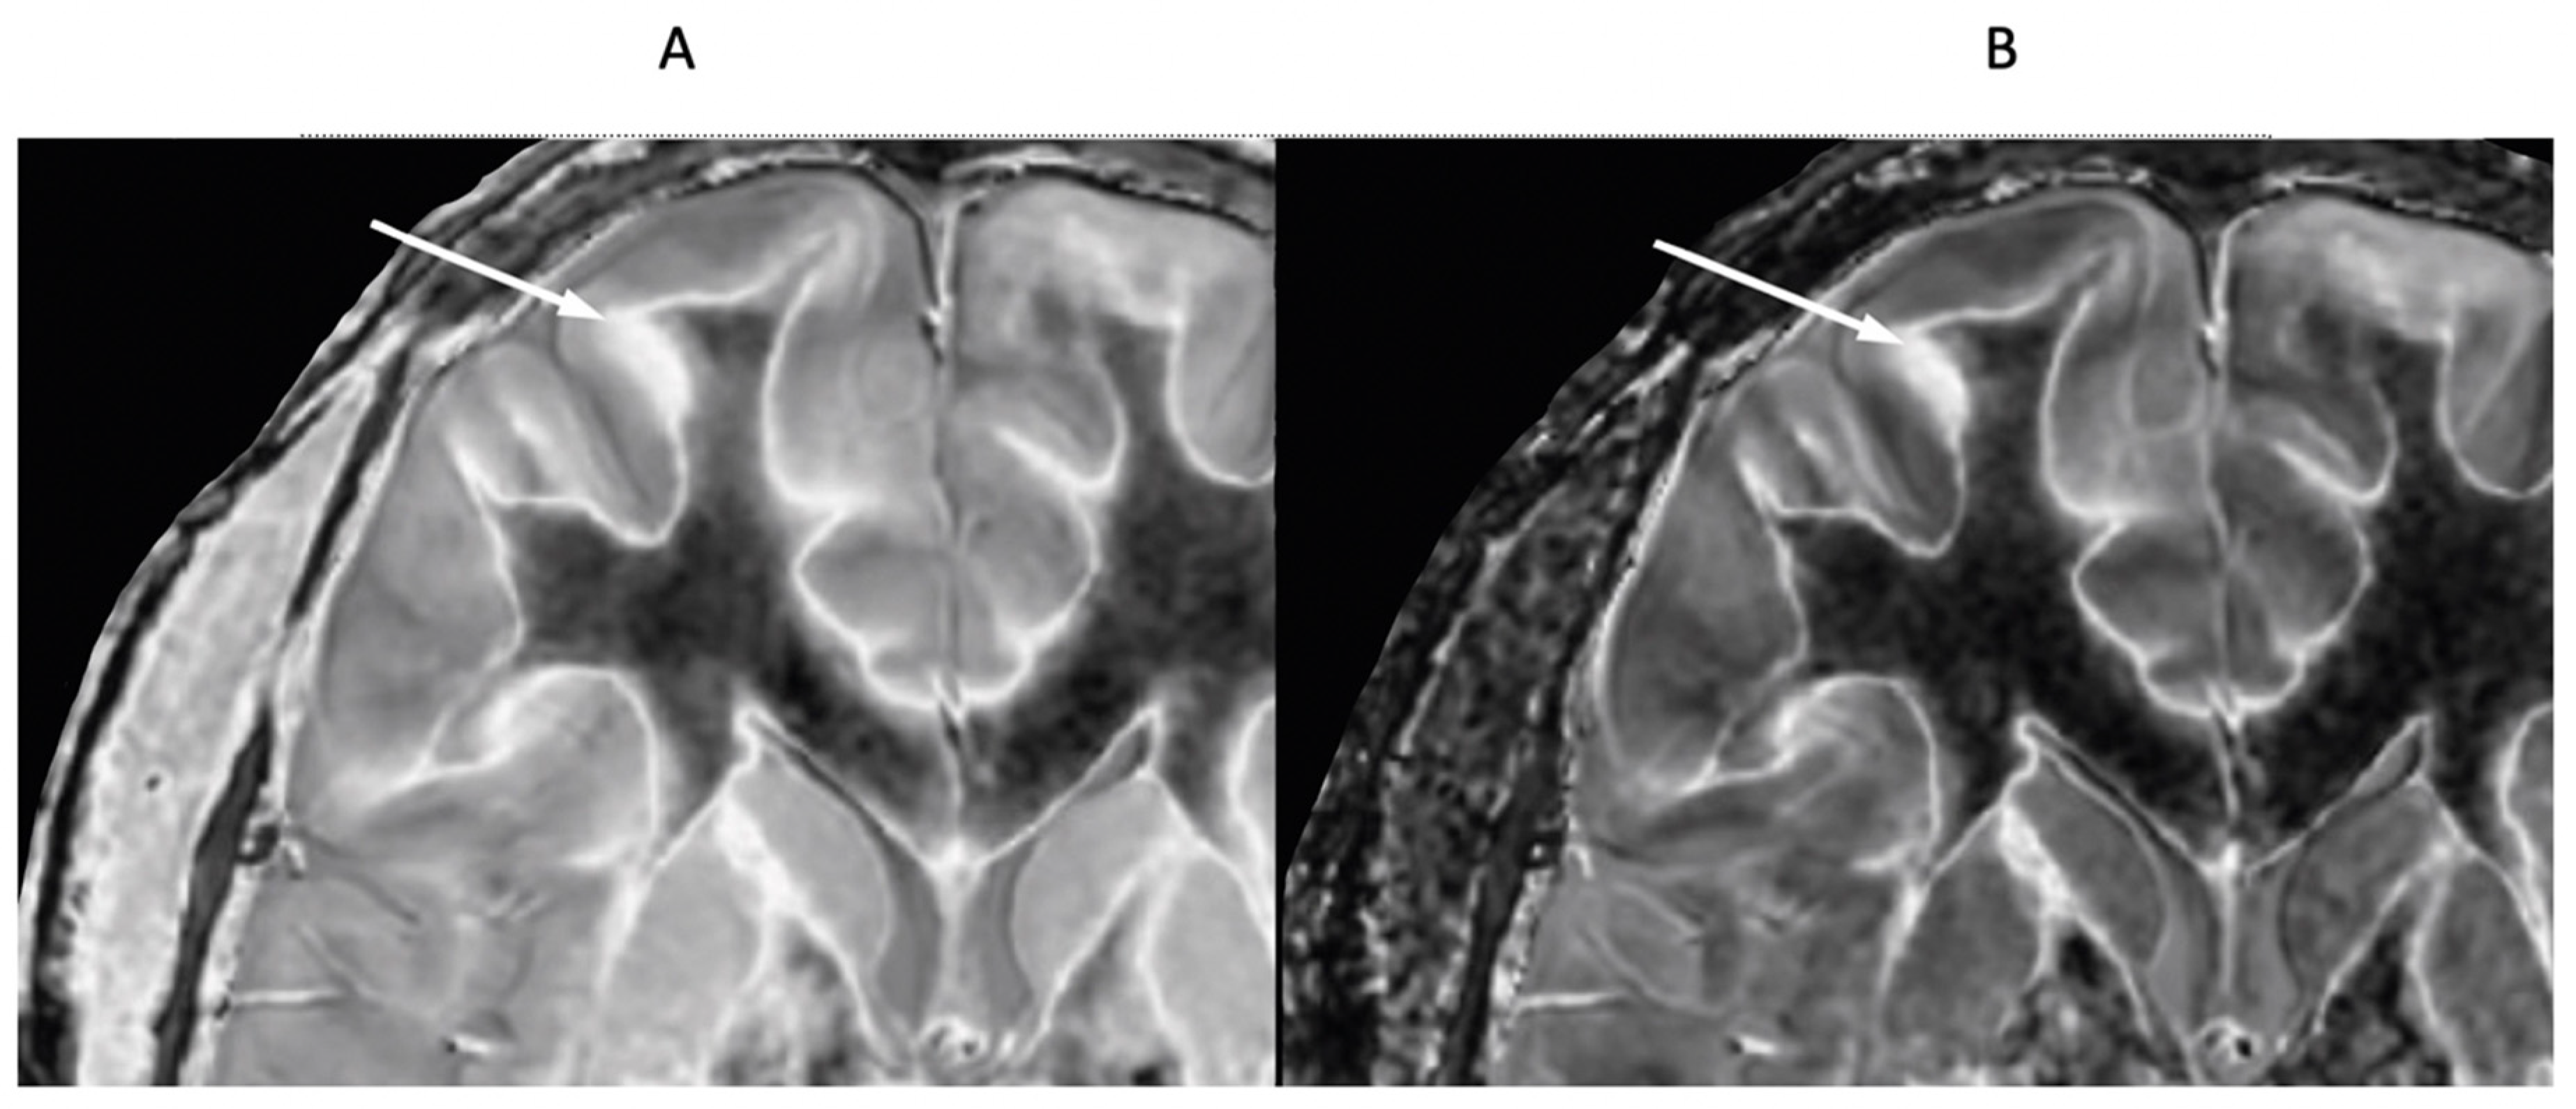

Figure 23.

41-year-old female patient with MS. A leukocortical lesion in the right medial frontal region is shown on the narrow mD dSIR image (A) and a matching lSIR image (B) (arrows). There are also left to right profiles with signal plotted against position (in mm) for the dSIR (blue) and lSIR (orange) images (C) at the level of the horizontal arrows shown in (A) and (B). No boundary between white matter and gray matter is seen within the lesion in (A). A disrupted high signal boundary between white matter and gray matter is seen in the lesion in (B). The lSIR profile (orange) has higher signal and steeper slopes than the dSIR profile (blue) in (C). The difference in signal (or contrast) achieved for the same change in position is generally greater with the lSIR filter i.e., the contrast shown on the lSIR image generally has a higher spatial resolution.